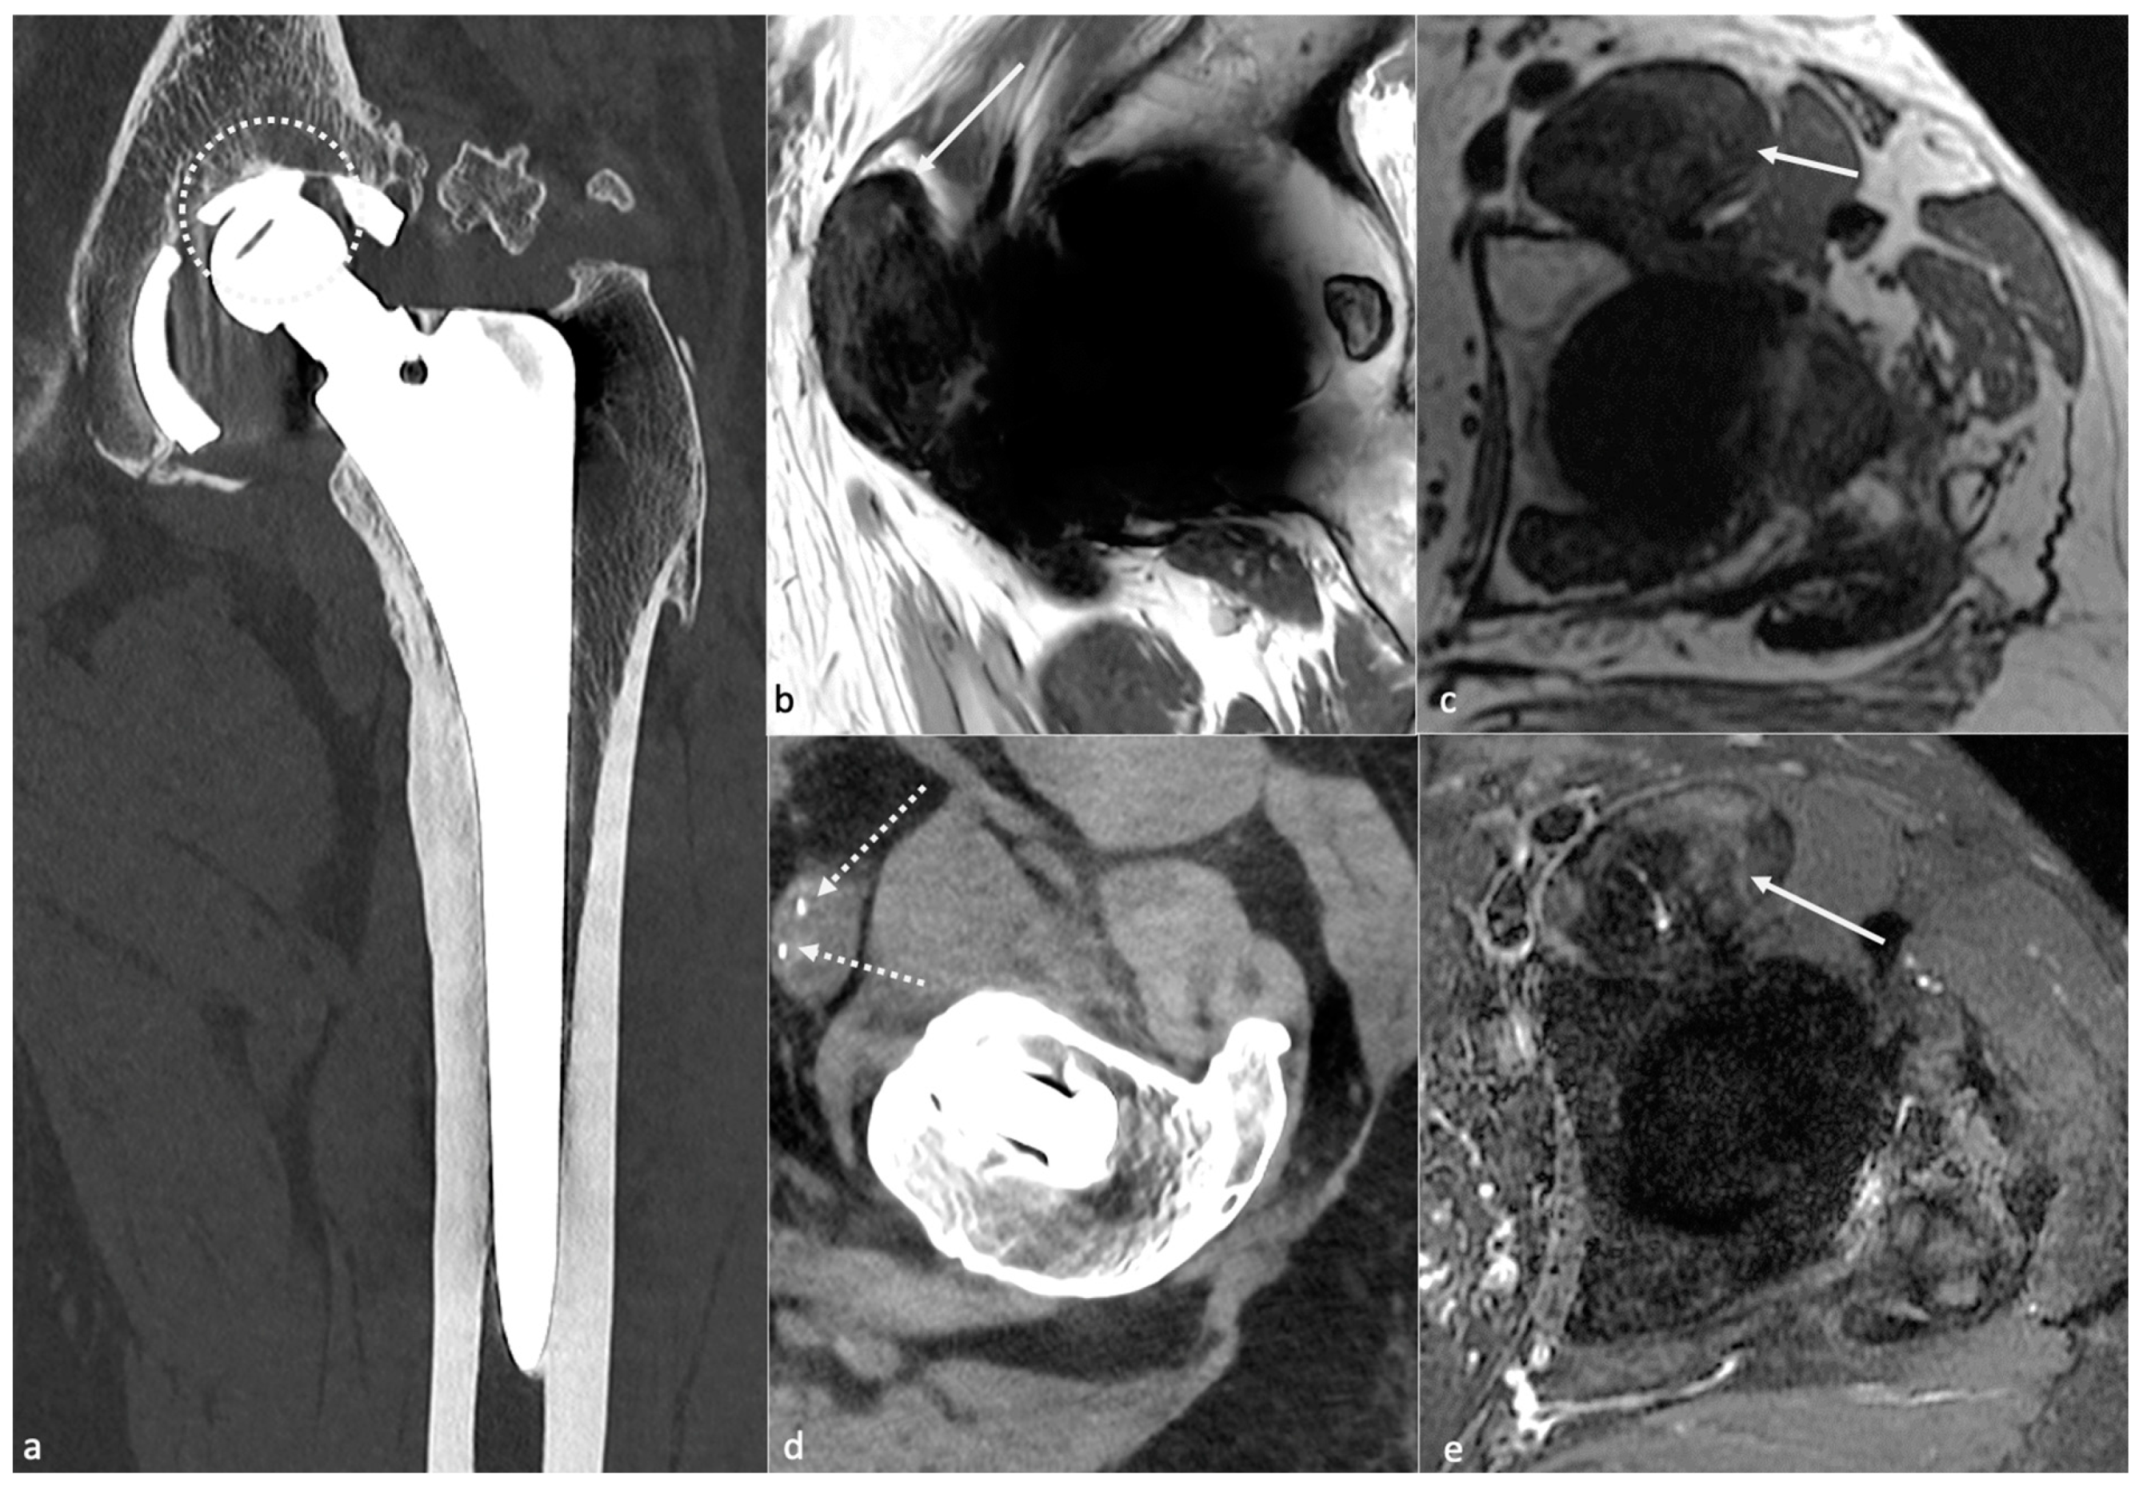

- Metallosis results from the shedding of metallic debris (secondary to a MoM prosthesis with corrosion, a conflict between a metallic acetabular cup and the prosthetic neck, or a contact between a metallic head and an acetabular metal back in case of PE wear or dislocation) that induces synovitis and an indolent pattern of osteolysis, potentially leading to loosening (i.e., potentially looking similar to osteolysis and PE wear). Synovitis may contain low-signal intensity or metallic density debris, causing MRI artifacts and bone erosion, best depicted on CT-MAR (Figure 20). Such debris might also be located in periprosthetic soft tissue and lymph nodes [54,57]. Metallic debris presence might also accentuate PE wear (i.e., third fragment wear) [54]. Of note, high serum metal-ion levels can be found in symptomatic and asymptomatic patients and would be associated with pseudo-tumors, so that such a biological finding should lead to the prescription of an MRI to rule out a pseudo-tumor even in asymptomatic patients [6,103].

- Additionally, referred to as trunnionosis, trunnion corrosion corresponds to a soft-tissue reaction to metal debris released from micromotion and mechanical wear at the head–neck or neck–stem junction of modular MoP HA. On MRI, it manifests as an adverse local reaction associated with medial calcar resorption [11,104].